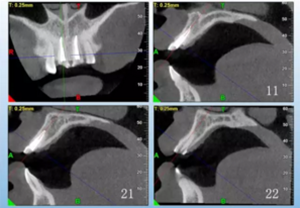

患者,女性,23歲,外傷導(dǎo)致上前牙折斷3天。檢查:中微笑 線;上頜右側(cè)中切牙至左側(cè)側(cè)切牙殘根,不松動,腭側(cè)缺損達(dá)齦下5mm, 牙齦中等厚度,齦緣基本完好。CBCT顯示:根長約11mm,牙根長軸與牙 槽突方向基本一致,唇側(cè)骨板完好、厚度1.0mm,可用骨高度21mm。全身情況良好。

圖3 術(shù)前CBCT